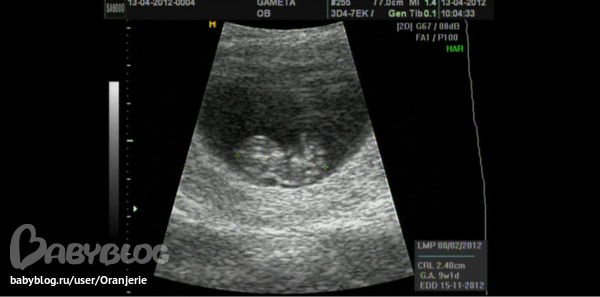

Вот наше чудо в 9 недель и 1 день, уже совсем человечек)))

Просто седцебиение есть уже в 5,5-6 недель. А порассматривать пальчики и ножки реальнее на первом плановом узи, которое делается на сроке 11 недель 1 день - 13 недель 6 дней.